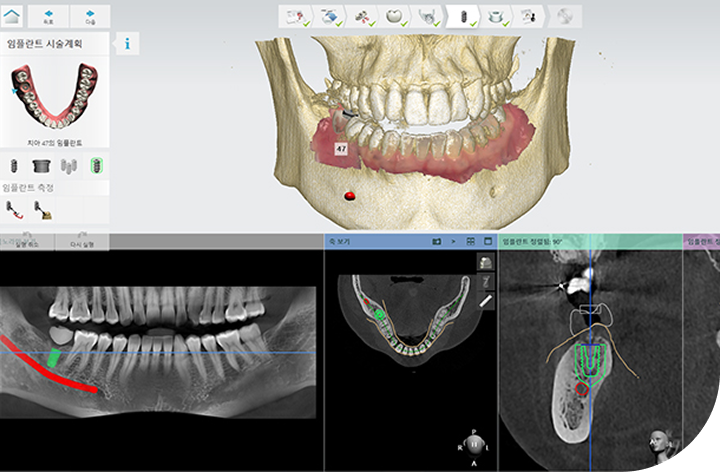

환자의 구강 정보를 디지털 데이터를 기반으로 3D 가상 모의 수술을

진행해 기존 방식 대비 수술 시간이 짧아 체력적 부담을 줄여주고

최소 절개로 통증 및 붓기 최소화로 면역력이 약하거나 회복력이 더딘

고령의 환자, 고혈압 당뇨 등 전신질환을 앓고 계신 분들도 부담없이

안전하게 수술받을 수 있습니다.

성공적인 임플란트 식립을 위해서는 정밀한 진단이 필수적입니다.

3D-CT, 구강 스캐너 등 다양한 디지털 장비를 이용하여

치아, 잇몸뼈, 신경 위치 등을 정확하게 파악해 수술 오차를 최소화하고,

통증 및 출혈을 줄여 더욱 안전하고 편안한 임플란트 식립이 가능합니다.